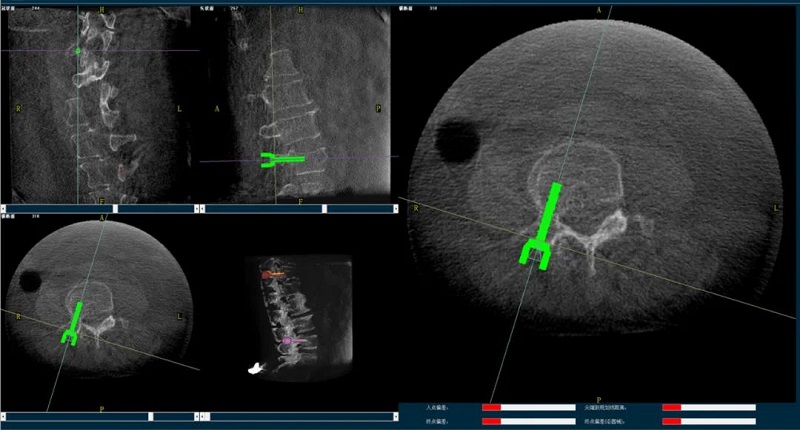

(2)醫(yī)生制定個(gè)性化的手術(shù)方案,在機(jī)器人導(dǎo)航界面上進(jìn)行路徑規(guī)劃;

(3)根據(jù)設(shè)定好的的位置和入針?lè)较?,植入引?dǎo)針;